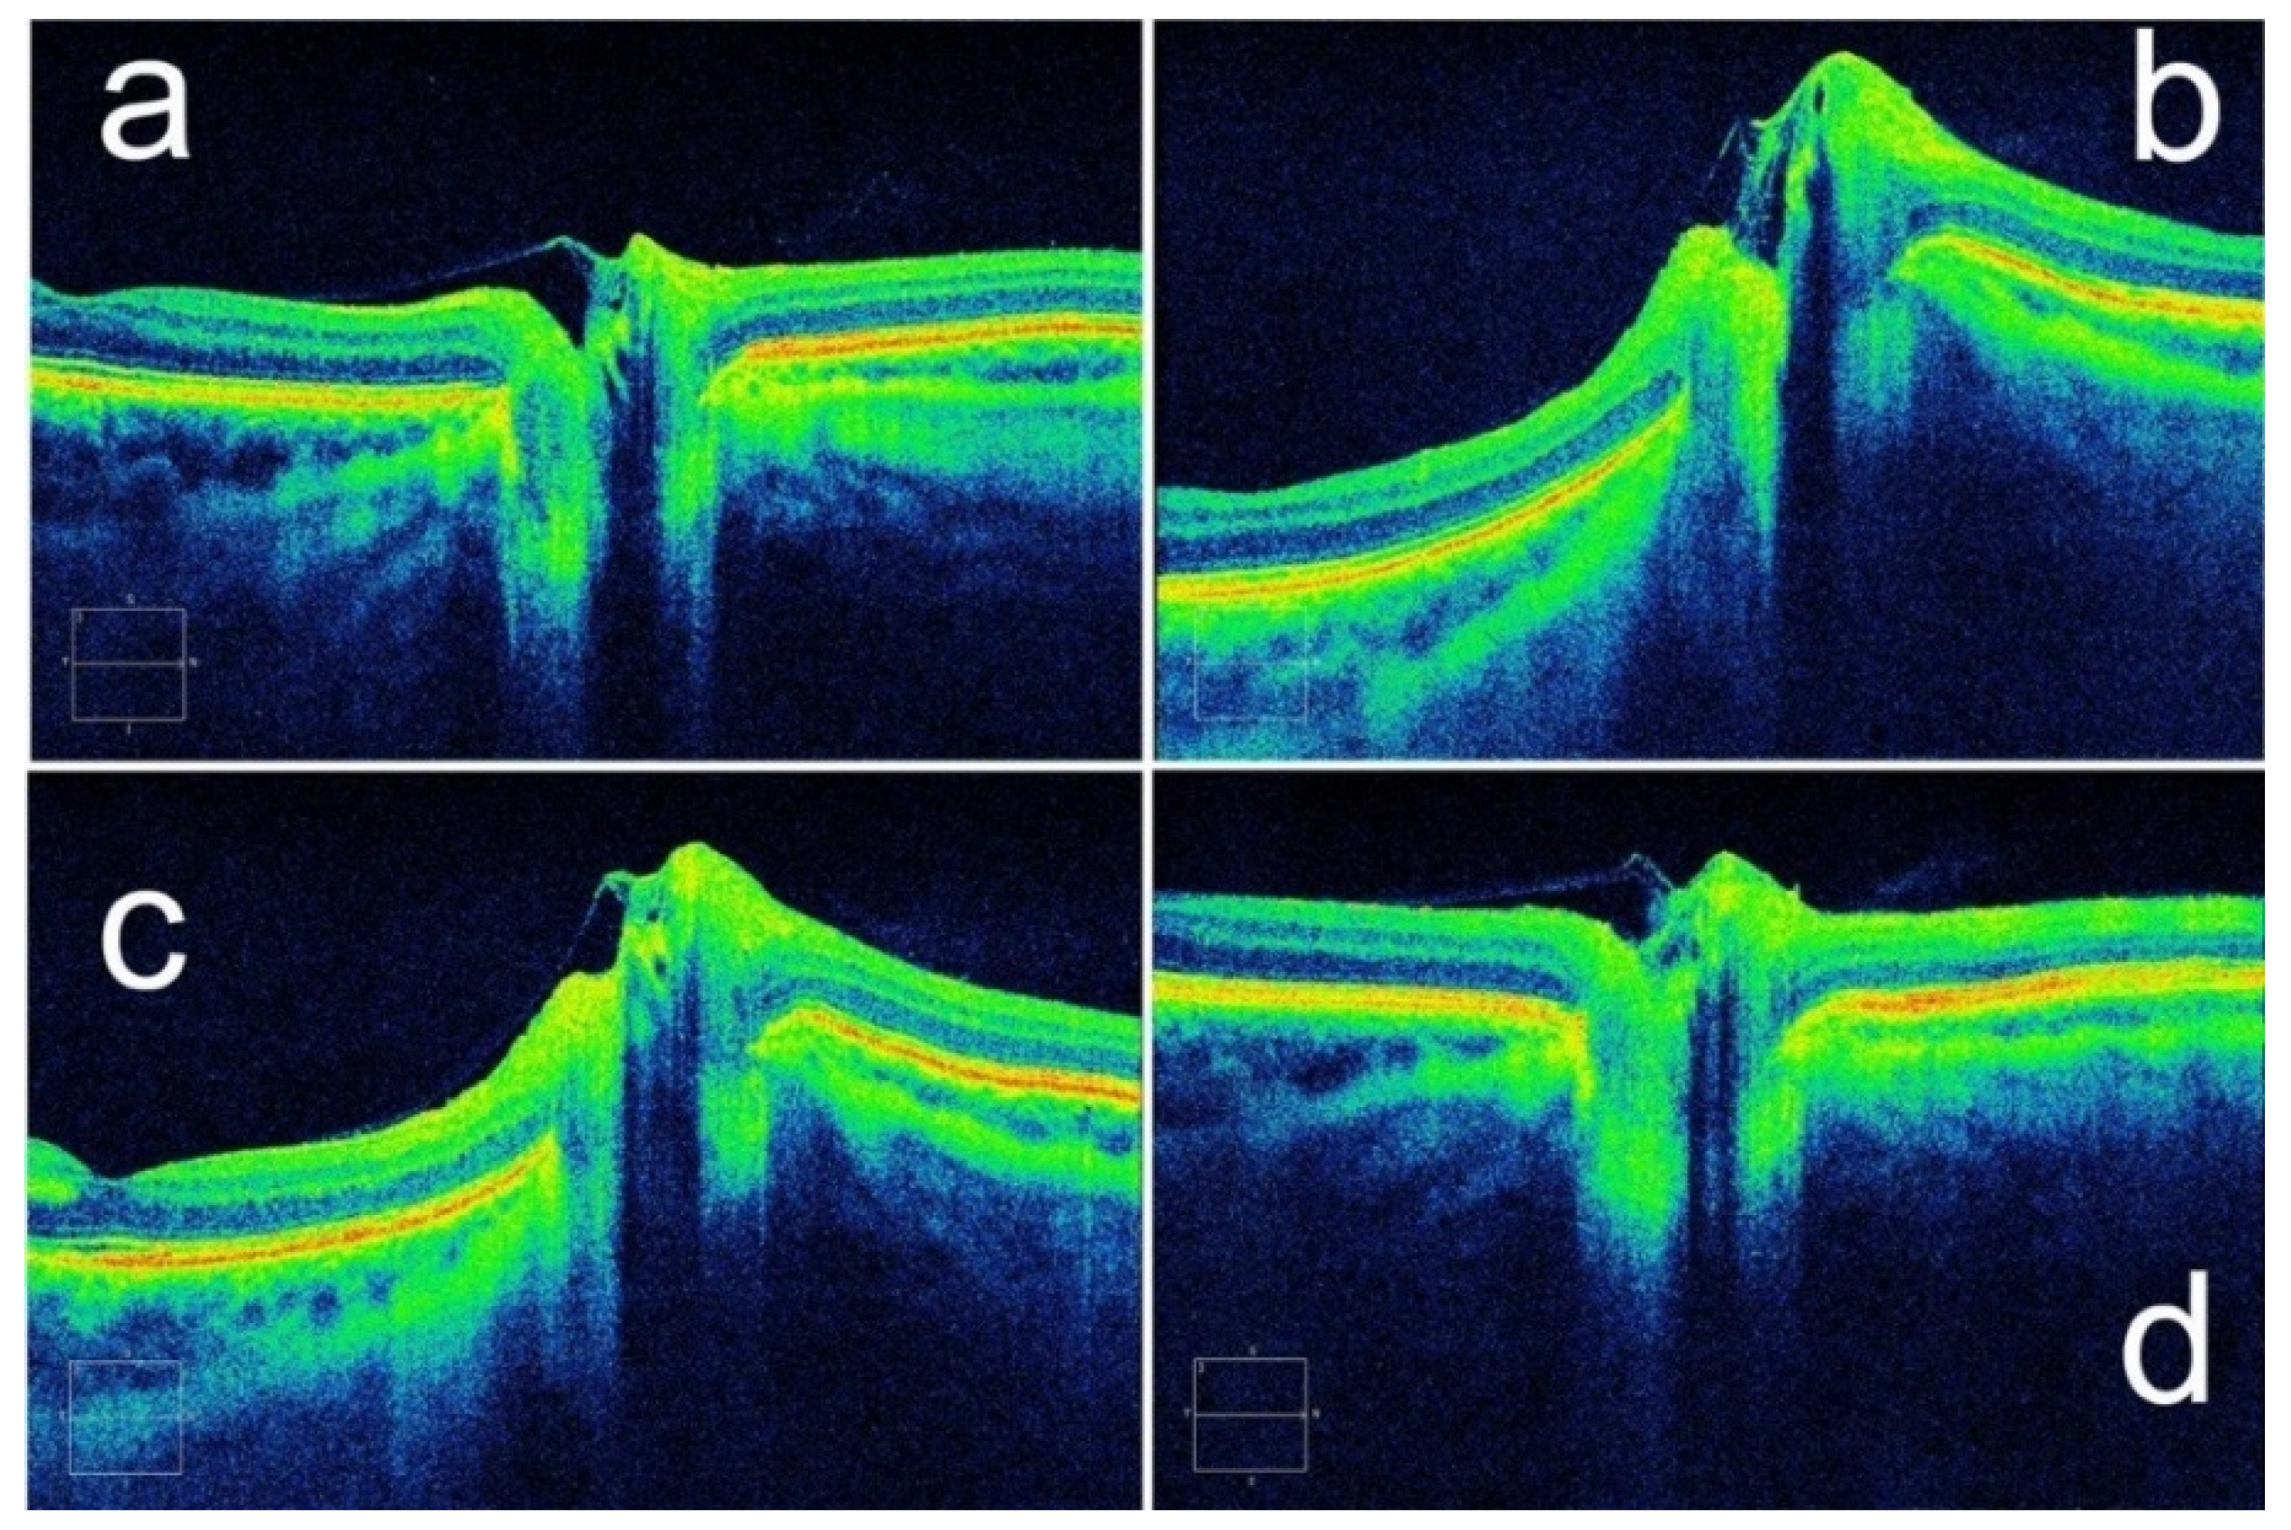

- Kupersmith, M.J.; Sibony, P.; Mandel, G.; Durbin, M.; Kardon, R.H. Optical coherence tomography of the swollen optic nerve head: Deformation of the peripapillary retinal pigment epithelium layer in papilledema. Investig. Ophthalmol. Vis. Sci. 2011, 52, 6558–6564. [Google Scholar] [CrossRef] [Green Version]

- Sibony, P.; Kupersmith, M.J.; Honkanen, R.; Rohlf, F.J.; Torab-Parhiz, A. Effects of lowering cerebrospinal fluid pressure on the shape of the peripapillary retina in intracranial hypertension. Investig. Ophthalmol. Vis. Sci. 2014, 55, 8223–8231. [Google Scholar] [CrossRef] [Green Version]

- Jacobsen, H.H.J.K.; Moe, M.C.; Petrovski, G. Non-invasive Estimation of Pulsatile and Static Intracranial Pressure by Optical Coherence Tomography. Transl. Vis. Sci. Technol. 2022, 11, 31. [Google Scholar] [CrossRef]